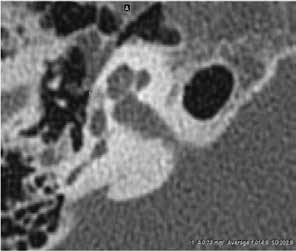

Figure. A: In this CT image of temporal bone, the arrow points to the hypodense otosclerotic focus at the right fissula ante fenestram. B: Oval region of interest measures the density of the otosclerotic focus (size is 0.73 mm2, CT value: 1,014.9 HU). C: Oval region of interest measures the density of the normal temporal bone (size is 0.73 mm2, CT value: 1,659.4 HU), with a density ratio of 0.611.